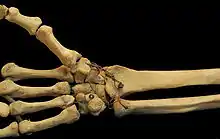

Thumb

Bones of a human wrist. In this photo both the free position and the saddle shape of the first CMC joint and the proximal transverse palmar arch are clearly visible.